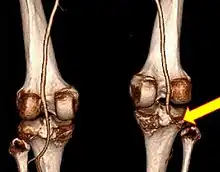

Plain X-rays, CT scan, ultrasonography, or MRI may help with the diagnosis.[2][11] Findings on X-ray that may be useful among those who have already reduced include a variable joint space, subluxation of the joint, or a Segond fracture.[5]

They may be divided into five types: anterior, posterior, lateral, medial, and rotatory.[4] This classification is based on the movement of the tibia with respect to the femur.[11] Anterior dislocations, followed by posterior, are the most common.[2] They may also be classified on the basis of which ligaments are injured.[2]